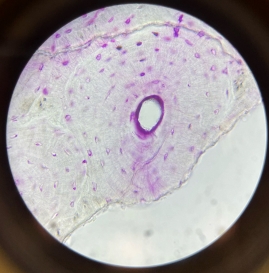

Muscular Arteries (Medium Sized Arteries)

Muscular Arteries (Medium Sized Arteries)

Muscular Arteries (Medium Sized Arteries)

Elastic Arteries (Aorta)

Elastic Arteries (Aorta)

Elastic Arteries (Aorta)

Large Veins

Large Veins

Large Veins

Large Veins